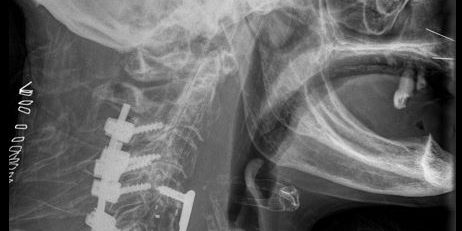

Πρόσθια – Οπίσθια (360ο) Σπονδυλοδεσία Αυχενικής Μοίρας Σπονδυλικής Στήλης